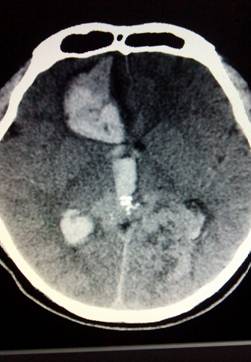

然而當(dāng)我們把CT片拿給她看,她沉默了……CT顯示的是:1.右側(cè)額葉出血破入腦室,出血量約40ml;2.蛛網(wǎng)膜下腔積血!